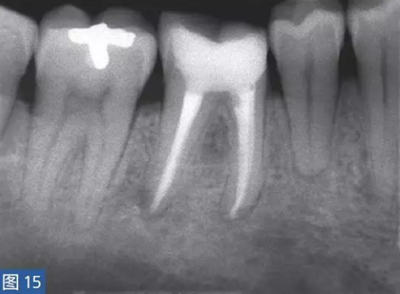

圖15:根管治療12 個(gè)月后的放射學(xué)檢查?;谂R床診斷,只有46 牙齒需要治療,因?yàn)樗歉獠∽兊闹饕±碓?